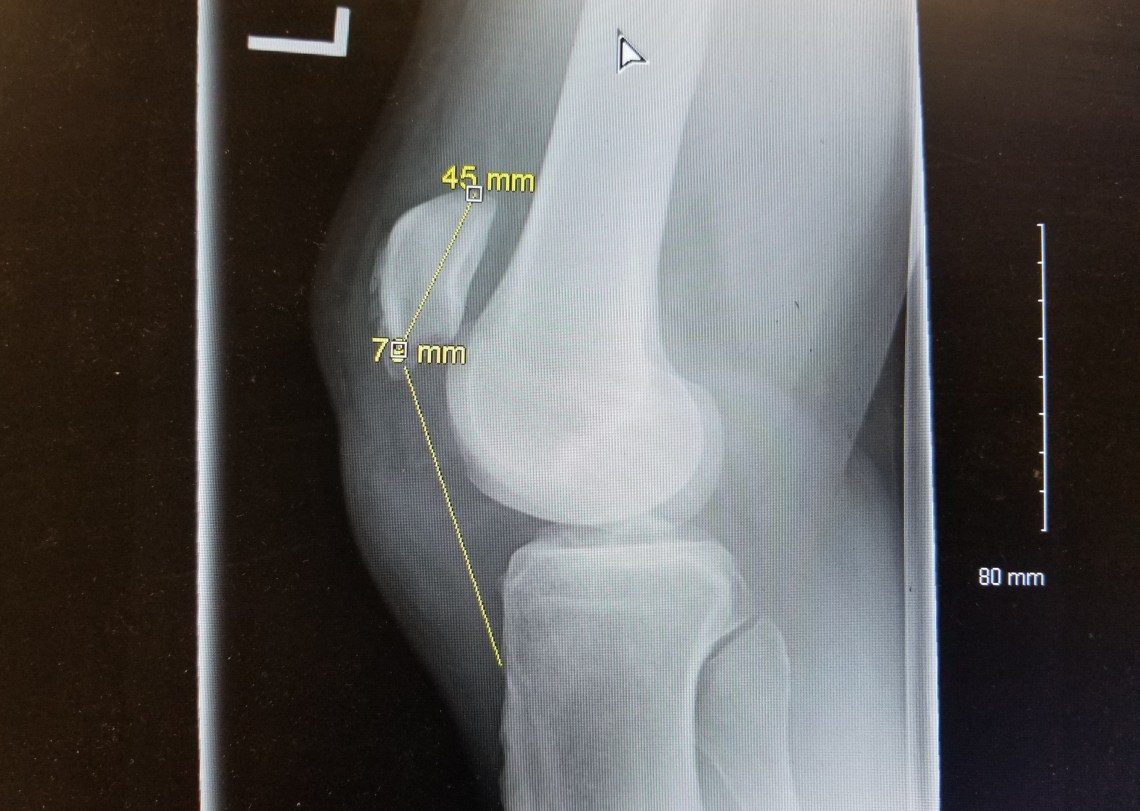

The radiographs are usually normal. In quadriceps rupture, an avulsion fracture of the superior pole of the patella may be seen whereas in patellar tendon rupture you may see a high-riding patella (Patella alta) on the lateral film. This can be appreciated using the Insall-Salvati ratio, where the patellar tendon length (distance from the lower pole of the patella to the tibial tuberosity) to patellar length (greatest pole-to-pole length) ratio is considered normal between 0.8 and 1.2. A ratio >1.2 is considered a patella alta, suggestive of patellar tendon rupture and a ratio <0.8 is considered a low riding patella, or patella baja, suggestive of quadriceps tendon rupture. This is best measured on lateral films with knee flexed 30 degrees.

The patient had an inability to straight leg raise, a palpable infrapatellar sulcus and a high riding patella on his radiograph. He was diagnosed with complete patellar tendon tear and orthopaedics were consulted in house for operative repair.